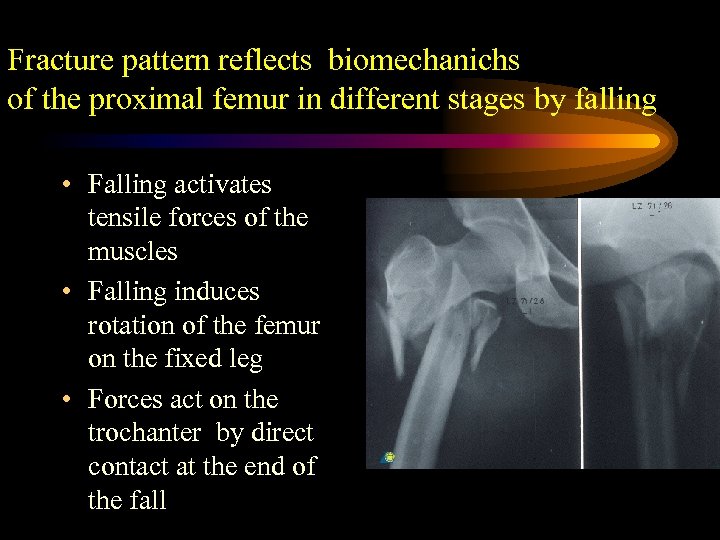

Fracture pattern reflects biomechanichs of the proximal femur in different stages by falling • Falling activates tensile forces of the muscles • Falling induces rotation of the femur on the fixed leg • Forces act on the trochanter by direct contact at the end of the fall

Fracture pattern reflects biomechanichs of the proximal femur in different stages by falling • Falling activates tensile forces of the muscles • Falling induces rotation of the femur on the fixed leg • Forces act on the trochanter by direct contact at the end of the fall